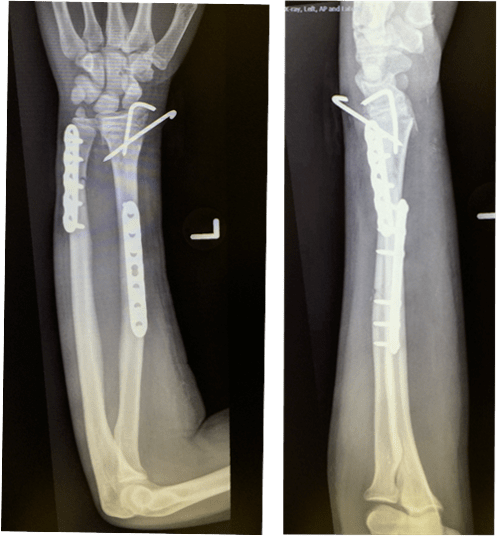

(图片)手术治疗前臂双骨折 - 好大夫在线

前臂尺桡骨骨折的手术治疗

前臂中段开放性双骨折